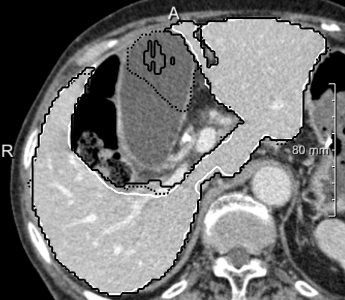

Example segmentations of the 2D U-net ensemble (2 mm) are illustrated in 3. Contour precision is limited by the resampling, but the model nicely excludes the vena cava and large hilar vessels much like in our training set. This hinders comparison against the state-of-art, since the reference masks from the SLIVER07 challenge (dashed in 3, right) partially include these vessels.

In most cases, the purely slice-wise application of the 2D U-net (dashed contours in 4) does not show any comb artifacts in orthogonal views. However, the ensemble classifier (solid contours) performs significantly better when the appearance is severely abnormal and 3D context is needed. In some cases, it locally performs worse, but has an overall better volumetric overlap (Wilcoxon signed-rank test, ). The ensemble models performed significantly better than the purely 2D transversal model on the same voxel size.